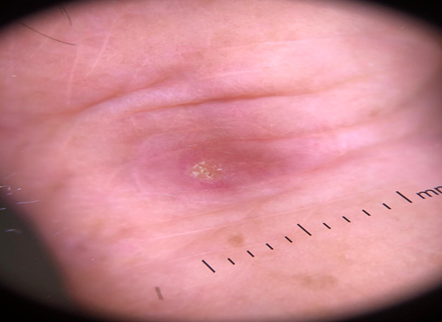

On physical examination, erythematous papules and nodules with a smooth surface, over the metacarpal-phalangeal and in the proximal and distal interphalangeal joints, hands and elbows were noted (Figures 1 & 2). Some of the lesions exhibited small areas of ulceration, covered by keratotic scales (Figure 3). Additionally, livedo reticularis was noted in the upper and lower limbs.

Figure 3 Dermoscopy showing a erythematous papule with a small area of ulceration, covered by keratotic scales.